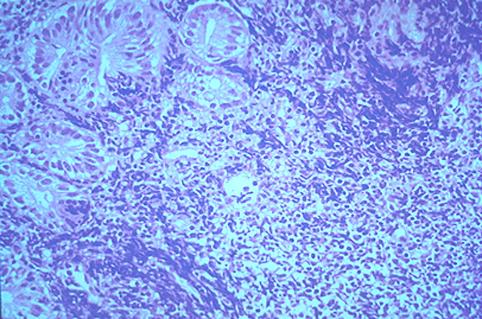

疾病(病理主体)的分类恶性淋巴系肿瘤/恶性淋巴瘤

部位(按器官分)十二指肠/球部

检查方法病理切片(微观)

肿瘤的肉眼分类0型(表在型)/IIc型(IIc)

肿瘤最大直径15~19